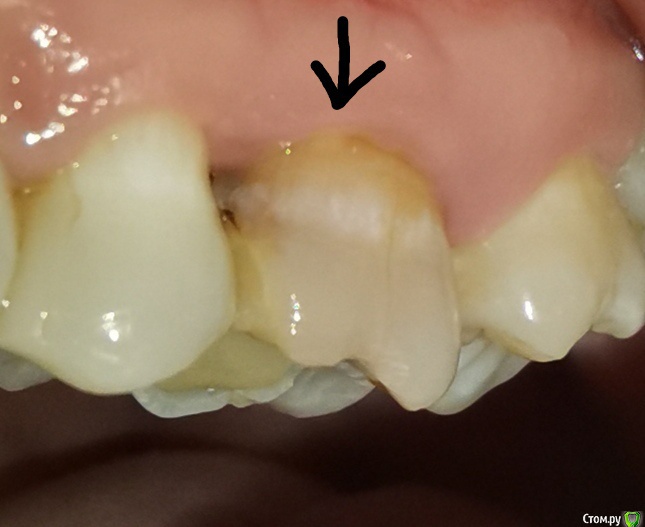

Здравствуйте. Лет 17 назад мне удалили нерв в верхней шестерке слева, оставив фрагмент инструмента. Пару дней назад об этом узнала. Хотела сходить к эндодонтисту, чтобы под микроскопом извлек, но присмотрелась и увидела, что зуб как будто треснул вдоль (вертикально). Видно с внешней и внутренней стороны. Теперь волнует, можно ли его сохранить или придется вырывать и ставить имплант?